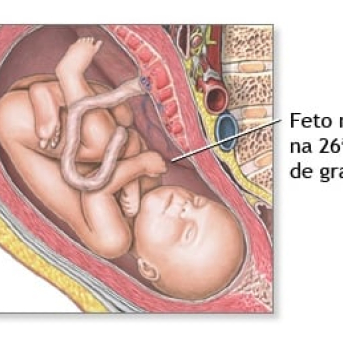

26 semanas

A grande dúvida sempre é: com 26 semanas são quantos meses? Na 26ª semana continuamos no 6º mês de gestação e seu pequeno bebê chegou a um peso de em média 1 kg, implicando que se quadriplicou nas últimas semanas. A partir de agora, seu corpo irá acumular gordura para suportar a temperatura fora da barriga, além de ser fonte de energia nos seus primeiros dias de vida após o parto3.

Devido ao ganho de peso, é natural no sexto mês da gravidez que a mulher comece a sentir dores lombares devido à postura, que se modifica pelo peso da barriga. O aconselhado é ficar o menos possível na mesma posição, devendo se alongar até mesmo para auxiliar na circulação sanguínea, evitando inchaços. Assim termina o segundo trimestre da gravidez.